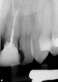

Din cele 109 implante inserate la cei 69 pacienţi în cursul unei perioade de 4 ani, nu s-a înregistrat niciun eşec implantologic după inserţia dispozitivelor fixe şi restaurarea protetică ulterioară. La descoperirea implantelor, nu erau semne de mobilitate a acestora, şi toate implantele inserate au fost restaurate. În momentul prelucrării datelor, toate implantele au rămas complet încărcate şi în funcţiune, rezultând o rată de supravieţuire de 100% (tabelul 1). Ca şi grup, implantele erau funcţionale şi încărcate de o perioadă medie de 2 ani, variind între 6-65 luni. Indiferent de tipul implantului, localizarea în alveolă, statusul de fumător, 100% din implante sunt în funcţiune şi actualmente (tabelul 1 şi fig. 1-9).